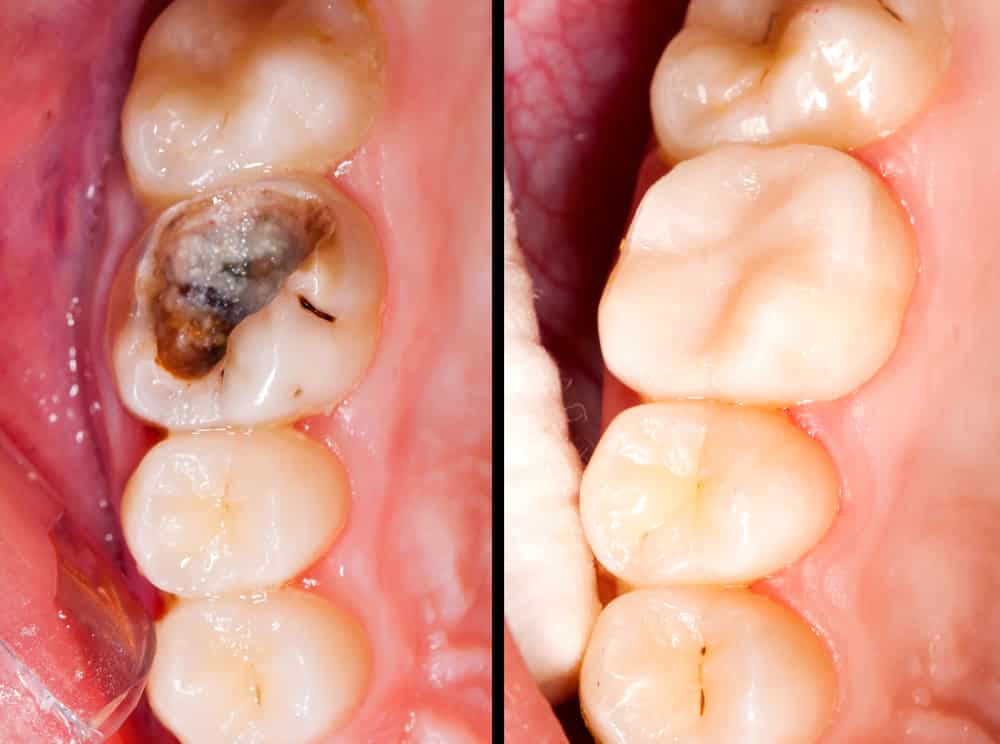

ترمیم و پیش‌آگهی در درمان اندودنتیک

۱. اهمیت ترمیم نهایی

• موفقیت درمان ریشه تنها به کیفیت اندودنتیک وابسته نیست؛ ترمیم تاجی مناسب به همان اندازه حیاتی است.

• مطالعات (Ng et al., IEJ 2011) نشان داده‌اند که کیفیت ترمیم کرونال، هم‌تراز با کیفیت درمان اندودنتیک در موفقیت طولانی‌مدت اثرگذار است.

۲. زمان‌بندی ترمیم

• بهترین زمان: بلافاصله یا در اولین فرصت بعد از اتمام درمان ریشه.

• تأخیر در ترمیم نهایی: ریسک نشت میکروبی و شکست درمان را به‌طور قابل‌توجهی افزایش می‌دهد.

• در دندان‌های با دیواره‌های ضعیف، اولویت با قرار دادن روکش برای افزایش مقاومت است.

۳. نوع ترمیم

• ترمیم‌های موقت (Cavit, IRM): برای مدت کوتاه بین جلسات یا تا زمان ترمیم دائم کافی هستند ولی دوام طولانی ندارند.

• ترمیم‌های کامپوزیت یا آمالگام: برای برخی دندان‌ها کافی هستند، اما در دندان‌های خلفی تحت فشار زیاد، روکش توصیه می‌شود.

• روکش کامل (Full Coverage Crown): در دندان‌های خلفی اندودنتیک، بهترین محافظت در برابر شکستگی را ایجاد می‌کند.